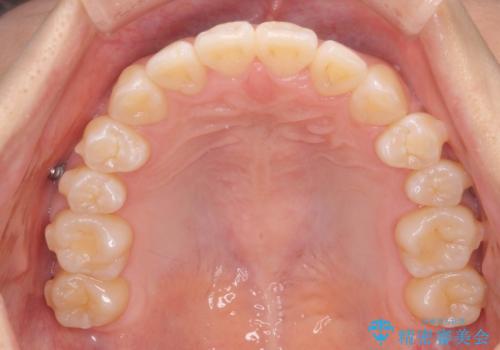

- 噛んだ時の前歯正中のズレ、引っ込んでいる前歯を治したい。と矯正治療を希望され来院されました。

左上2の前歯はスペースが足りないため、後方に引っ込んでしまっている状態です。

マウスピース矯正システムインビザラインで歯の後方移動、咬合関係の修正を行ったのち、引っ込んでいる左上2をワイヤーを用いて短時間で引き出す治療計画としました。

部分ワイヤー矯正を行なったことで約3ヶ月という短期間で前歯を綺麗に並べることができました。